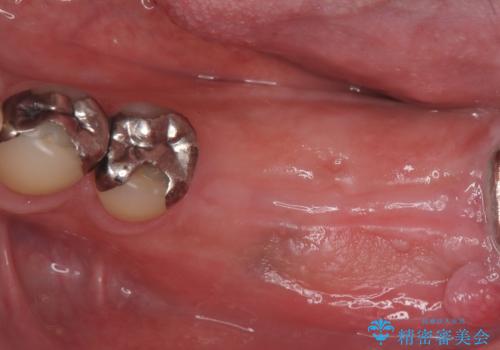

今回の治療では、まず左下6番と7番の欠損部に、骨の状態を考慮しながら慎重に2本のインプラントを埋入しました。インプラント体と骨がしっかりと結合するのを待った後、最短の期間で最終的な被せ物を装着するための精密な型取りを実施。最終的に、周囲の歯と調和した審美性の高いセラミック製の歯を装着しました。

治療期間は約3ヶ月で完了。以前の入れ歯のような煩わしさや動く心配がなくなり、天然歯と変わらない強い力でしっかりと食べ物を噛み砕けるようになり、快適な食生活を取り戻していただけました。